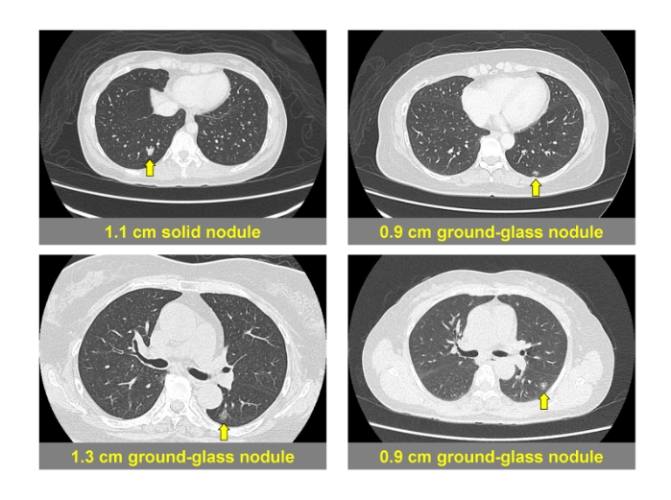

影像特徵解讀

我們看電腦斷層影像,不只是看"有"或"沒有",更要看細節:

- 密度:是均勻的純毛玻璃?還是混雜了實性成分(稱為部分實性結節)?實性成分的比例和大小至關重要。

- 大小:精確測量整體直徑和實性成分直徑(如果存在)。

- 形狀與邊緣:邊緣是光滑、模糊,還是有分葉、毛刺狀?內部有沒有空泡或支氣管充氣徵?

- 位置:位於肺的哪一葉?週邊還是靠近中央?這影響手術處理的難易度。這些特徵共同構成我們對這個毛玻璃結節病灶風險的初步判斷。